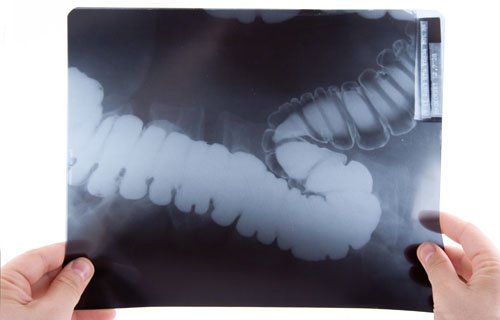

Рентген кишечника

– это комплексное исследование, позволяющее оценить его моторную и эвакуаторную функцию, а также выявить дефекты его структуры (язва, опухоль). Важным преимуществом этого метода является низкая стоимость, простота подготовки и возможность оценить состояние кишечника в режиме реального времени (рентгеноскопия) и одновременно с этим сделать снимки.

Петли кишечника плохо визуализируются даже при использовании современной рентгенологической установки. Чтобы правильно оценить состояние кишечника, применяется контрастирование. В большинстве случаев используется сульфат бария – белая жидкость с характерным привкусом. При проведении ирригоскопии применяется двойное контрастирование – вводится сульфат бария и инертный газ (или газовоздушная смесь).